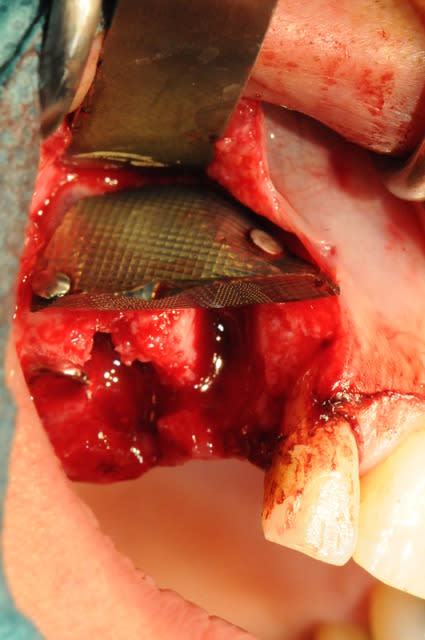

ici , fracture 13-14:

rog avec membrane titane

correction esthétique du niveau des collets de 12 et 11 (forte égression originel de 13-12-11 par rapport au secteur 2)